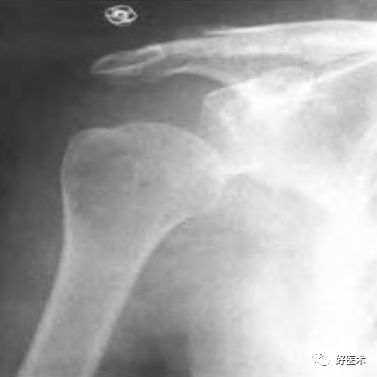

肱骨近端骨折中有85%左右为轻度移位骨折,Neer分型中:一部分骨折常采取保守治疗;二部分骨折中,部分外科颈骨折可以保守,大结节撕脱明显移位的需手术治疗;三、四部分骨折只要情况允许,应尽可能手术治疗。

(1)手术治疗: